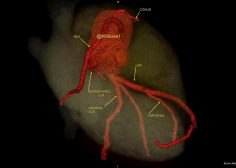

36Y male with chest pain, CT coronary shows a very rare anomaly. Twin LCX, (less than 10 cases in literature ).

The original LCX originates from LMCA , it supplies an early OM.

The 2nd anomalous LCX (arises from proximal RCA) with retro-aortic course till it reaches the left AV groove where it supplies a small OM.